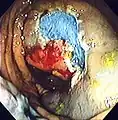

Polyp is identified.

A sterile solution is injected under the polyp to lift it away from deeper tissues.

A portion of the polyp is now removed.

The polyp is fully removed.